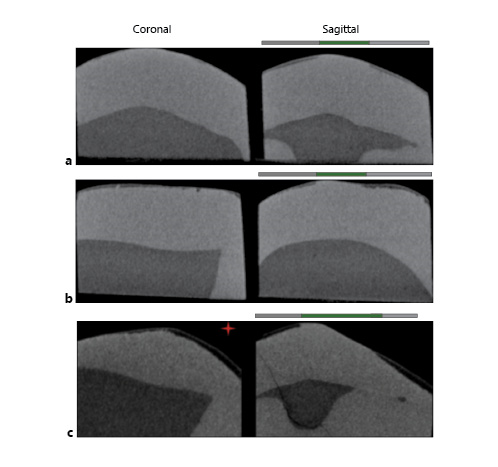

3-Dimensional X-Ray Micro-CT

Samples were scanned by 3-dimensional X-ray micro-CT (Skyscan 1,172, Bruker MicroCT, Kontich, Belgium) along with a reference standard (1-mm thick aluminum wire of high purity >99.999%; Sigma-Aldrich, St. Louis, USA) and linear attenuation coefficient of 0.767326/cm. For image acquisition, a 4.88-μm pixel, 100-kV voltage (a peak emission energy of 59 keV; according to the manufacturer), a 100-μA amperage, 180°-rotation, 3-frame average, 0.5°-rotation pitch, and AlCu filter were used. The images were reconstructed and converted to bitmap by nRecon software v1.5.23 with 10-smoothing, 18-ring artifact reduction and 25% beam-hardening. The images were aligned with the DataViewer morphometric visualization software (Bruker MicroCT). One 2-dimensional (2D) image was extracted from each of the 3 studied locations of the specimen, i.e., the occlusal (500 μm from the occlusal side), cervical (500 μm from the cervical side), and middle thirds. From each 2D image, 2 areas (left and right to the internal control) were analyzed, totaling 6 areas analyzed per sample (Fig. 1, sagittal view). The left and right outcomes were averaged and considered for the statistical analysis. The presence of wear facets was determined using 2D images in DataViewer software (Bruker MicroCT). The facets had a flat appearance (Fig. 1c). The anatomical location and the side where the wear facet was observed were tabulated and used in the data analysis.

Fig. 1

Micro-CT images. a Sample with young dental age. b Sample with advanced dental age. c Sample with wear facet (red star). Coronal sections show only the decayed area of the samples. Sagittal sections: gray lines signal areas exposed to demineralization. The green line signals the central area of the block that has been protected (internal control). Left side shows the wear facet.

ΔZ and LD analyses were performed using ImageJ software v1.8.0_66 by a previously trained examiner, who was blinded to the estimated dental age. ΔZ consisted of the difference in the mineral concentration profiles of the internal control and experimental enamel, up to a depth of 200 µm from the surface. The internal control and experimental profiles were 150 µm apart from each other. The quantification of the mineral concentration was performed from an equation described previously [Wong et al., 2004], using an enamel mineral empirical formula with a density of 2.99 g/cm3 [Elliott, 1997]. Based on the X-ray emission peak energy of 59 keV, the mass attenuation coefficient for enamel mineral was 0.406434 cm2/g, and the linear attenuation coefficient for aluminum was 0.767326/cm. Areas with mineral concentration <2.63 g/cm3 (corresponding to a mineral volume of 88%) in the control area and enamel blocks with <3 areas for analysis were excluded.